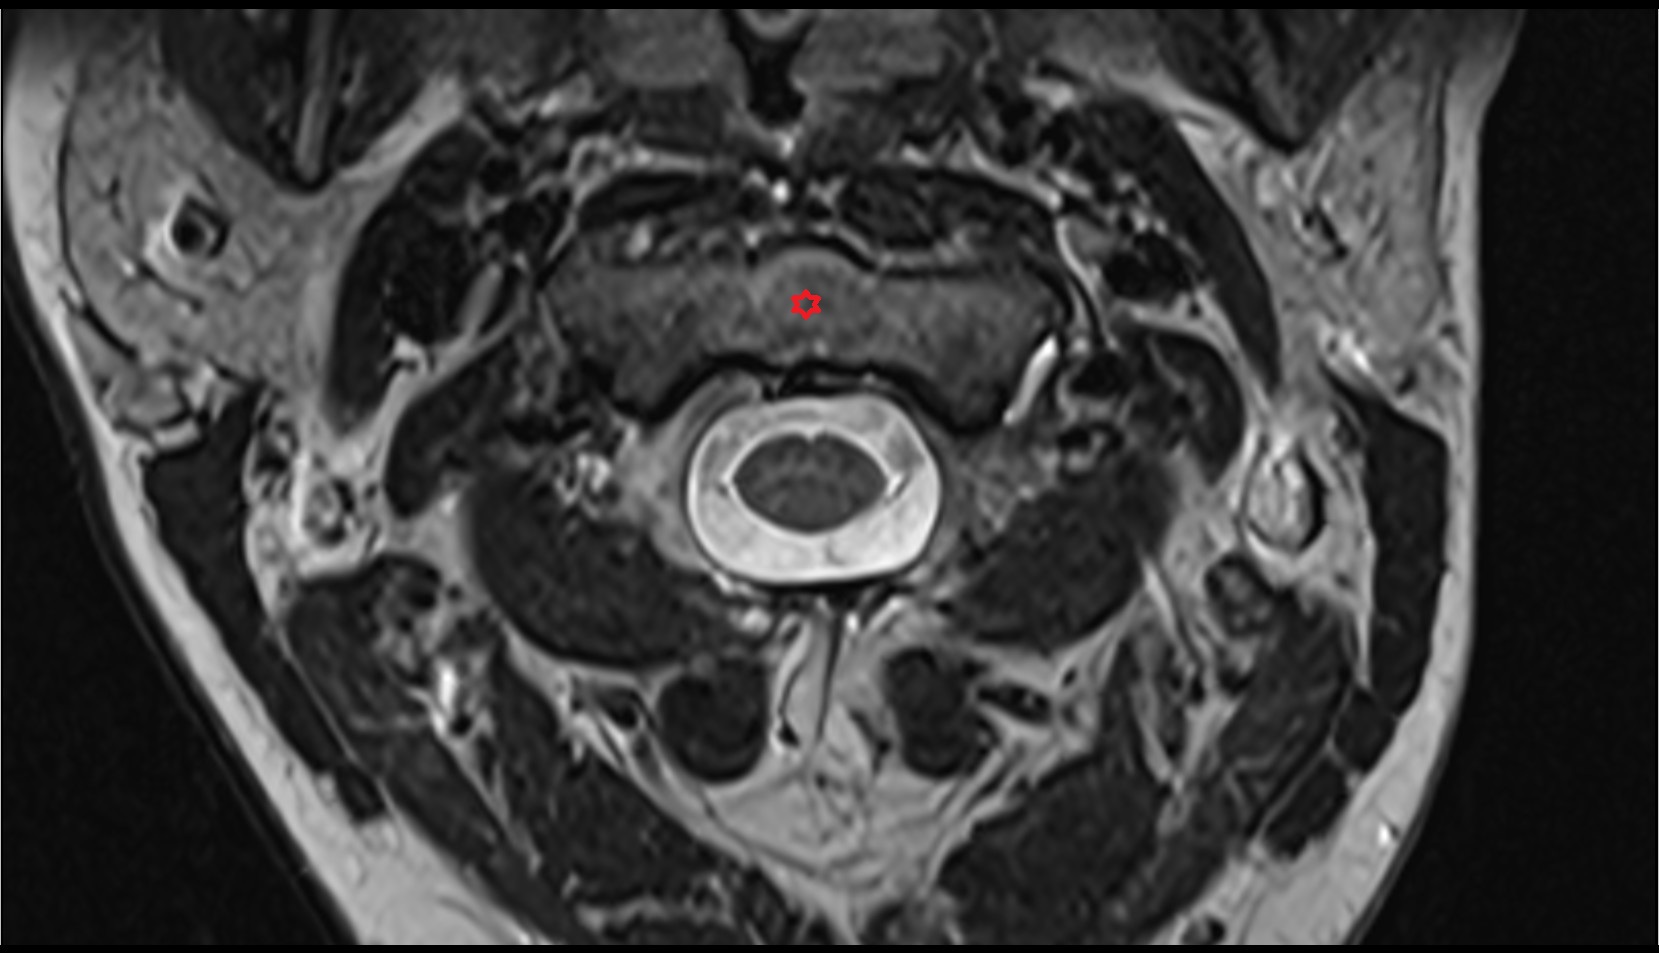

- Spinal cord

- subarachnoid space of spinal cord